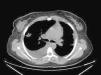

Se hicieron determinaciones analíticas en las que destacó una severa anemia microcítica e hipocrómica que requirió la administración de concentrados de hematíes. En los hemocultivos se aisló Staphylococcus aureus meticilín-sensible. Los anticuerpos antinucleares (ANA) y anticuerpos anticitoplasma del neutrófilo de patrón perinuclear (pANCA) fueron positivos a títulos bajos (no significativos), siendo los ANCA con patrón citoplasmático (cANCA) negativos. La radiografía de tórax mostraba dos opacidades pulmonares cavitadas en los campos derechos, compatibles entre otras posibilidades con émbolos sépticos. Debido a estos hallazgos radiográficos fue necesario descartar una endocarditis mediante ecocardiograma, que fue normal. En una tomografía axial computarizada (TAC) torácica se observaron las mismas lesiones cavitadas pulmonares (fig. 3).